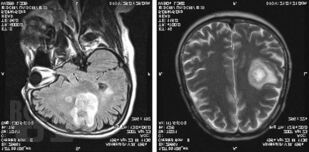

В руководстве представлены сведения о редко встречающихся (в том числе орфанных) неврологических синдромах и болезнях, сгруппированных в 4 главы в зависимости от этиологии: аутоиммунные и воспалительные; врожденные пороки развития нервной системы, наследственные и дисметаболические; опухоли нервной системы и паранеопластические синдромы; нейродегенеративные заболевания. В отношении каждой болезни представлены эпонимические сведения, шифр по МКБ-10, эпидемиология, этиология, патогенез, патоморфология, клиническая картина, диагностика, дифференциальная диагностика, лечение и прогноз. Все разделы книги иллюстрированы собственными клиническими случаями и результатами их обследований.